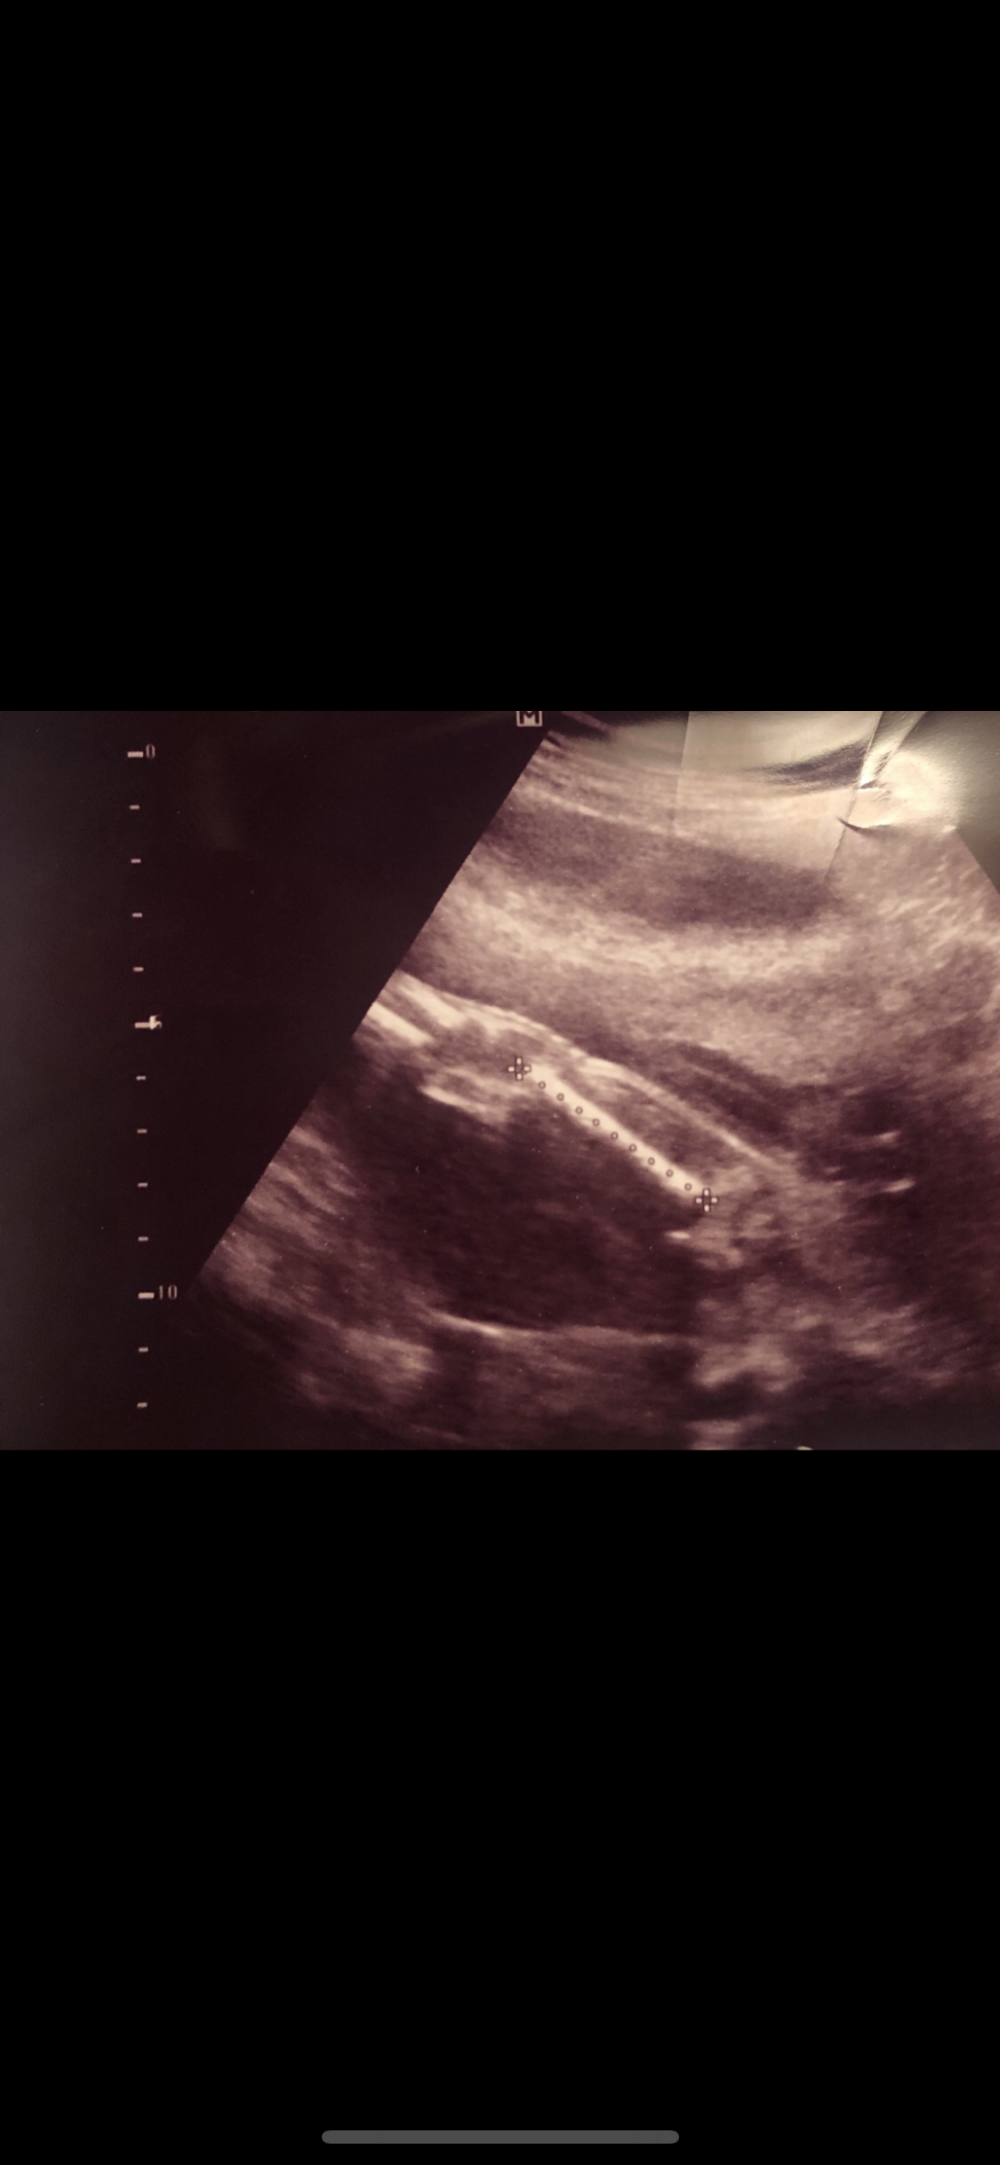

جلست ارتب اوراق المواعيد هذي صورة من اللي اعطتني الدكتورة الثانية اللي رحت لها امس ، اما دكتورتي الاولى مااعطتني ،،، كأنها عظمة الفخذ مع اني ماافهم بالسونار زين ولا شرحت لي وش جالسة تشوف ومافهمت زاوية التصوير ،، مبين الجنس في الصورة يابنات؟